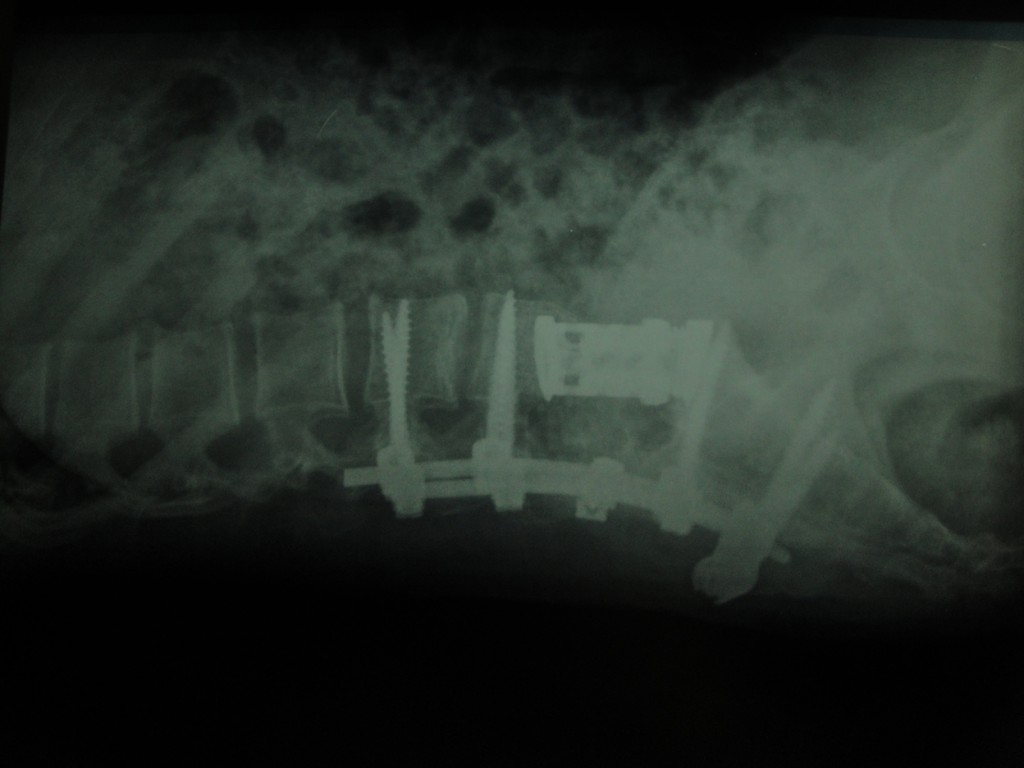

Tümörlere yaklaşım olarak doku tanısı çok önemlidir. O nedenle eğer tümörün odağı bilinmiyorsa ya da omurganın kendi tümörüyse öncelikle biyopsi almak gerekir. Ardından tümörün cinsine göre kemoterapi, radyoterapi, ameliyat ya da bunların kombinasyonu uygulanır.